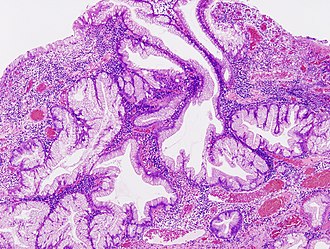

Hyperplastic polyp of the stomach. H&E stain. | |

| LM | abundant foveolar cells and elongated glands, +/-gland dilation |

Features:[2]

- Abundant foveolar cells and elongated glands - key feature.

- +/-Gland dilation.

- No atypical nuclei.

- No hyperchromasia.

- No loss of pseudostratification.

Micro

The sections show antral-type gastric mucosa with hyperplastic gastric pits. No gland dilation is apparent. The epithelium matures to the surface. The lamina propria is not expanded.

Focal neutrophilic inflammation is present. No Helicobacter-like organisms are identified. No intestinal metaplasia is present. No mitotic activity or nuclear atypia is apparent.